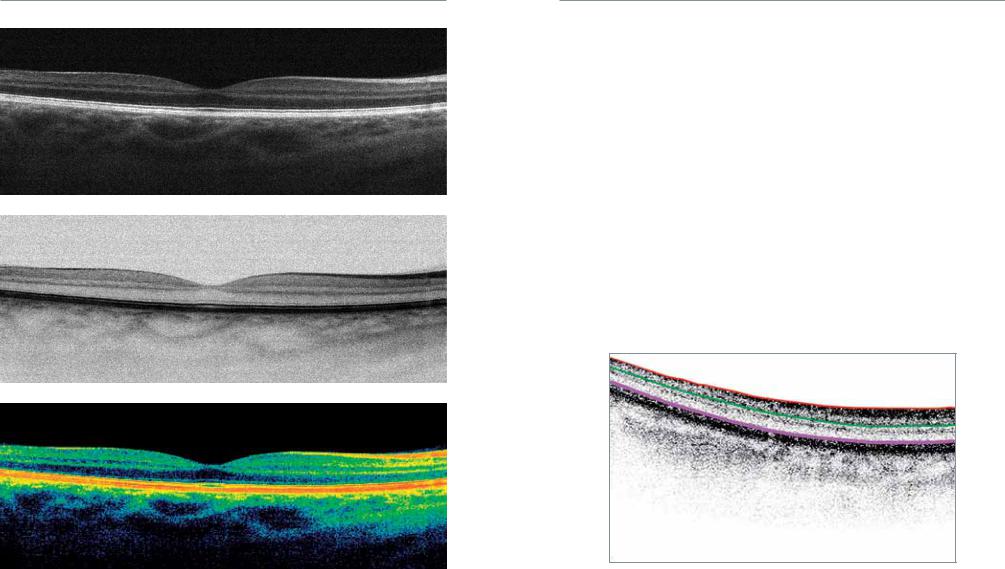

Диагностика зрения: Когерентная томография сетчатки

Раздел: Фотоальбом решений